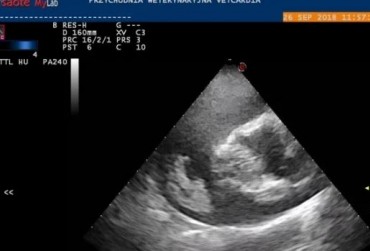

Obraz echo serca przez zabiegiem usunięcia worka osierdziowego 2

19 lutego 2019

Rafał Kraszewski

Czytaj więcej